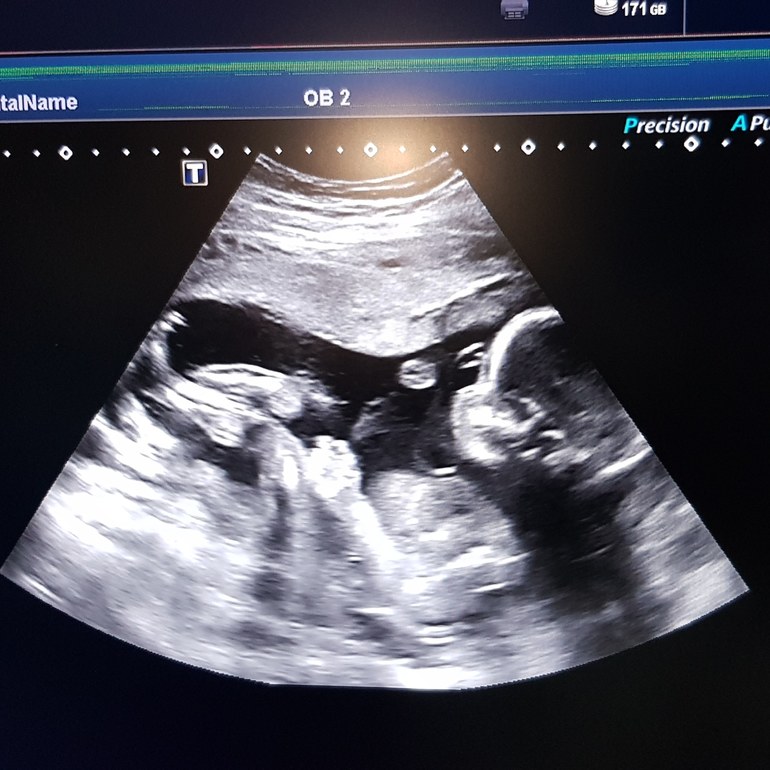

2 скрининг УЗИ в ЖК

Сходила наконец-то на скрининг УЗИ в ЖК. С лялечкой все в порядке, судя по заключению,узистка говорила, что все в норме.

Судя по всему быть мне дважды тещей 😂 Будет у нас вторая доченька. Сказали не 100%, зажимала ножки ляля, но ничего не вываливается между ножек. Говорит с характером девочка) не хочет нам свой пирожок показать😂

Срок по узи 20 недель, по месячным 20 и 4.

Такое четкое УЗИ! Так все видно хорошо :) Гарем это нечто другое. Легкой вам беременности и сил, а малышу спокойствия и уюта в мамочкином пузике!